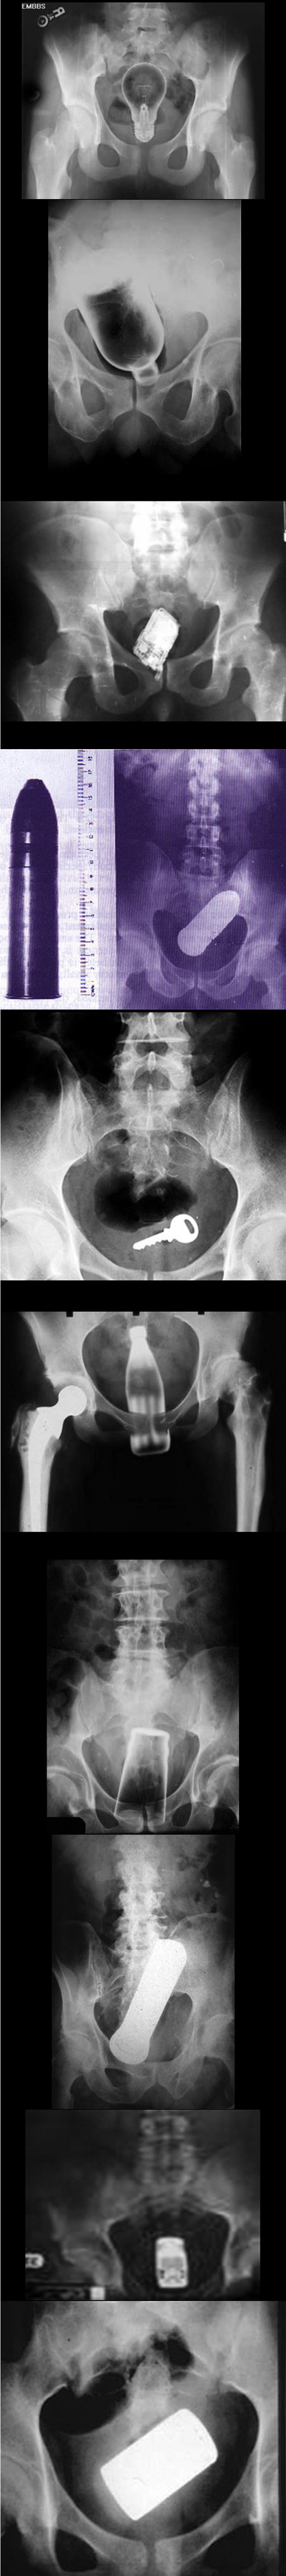

Redom: žarulja, plastična boca, mobitel, metak, ključevi, Coca Cola, čaša, baterija, autić, mobitel.